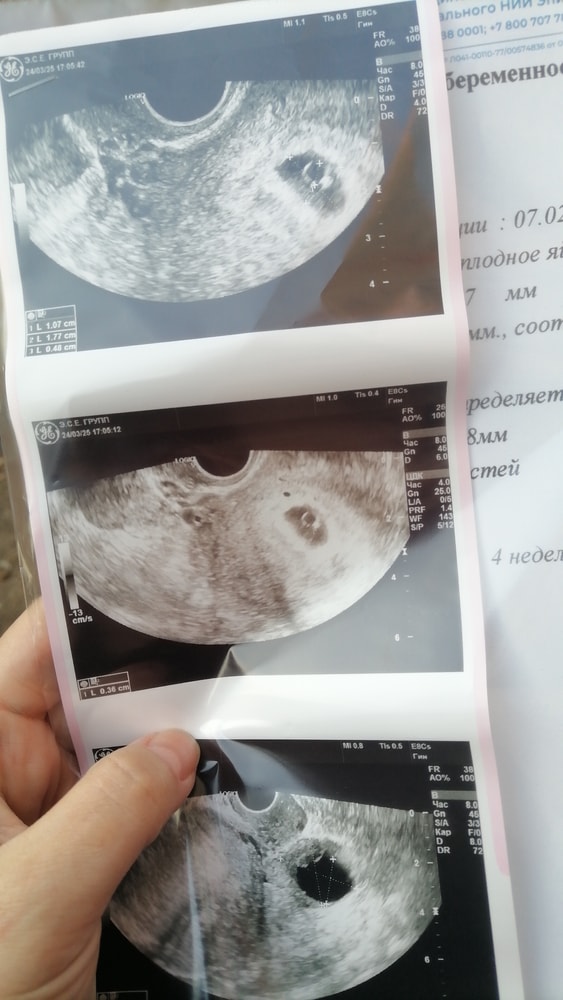

Фото узи есть, смотрю, это не эмбрион внутри ПЯ? Сказали, что его ещё нет- рано

Вот на снимке хорошо видно, колечко, это ЖМ, а точечка на нем, это эмбрион. Срок тут 6+3

если 3,2, то рано, у меня вот такой был на сроке 6 недель.

Но я, вроде, вижу, зарождающуюся горошенку у вас, будто отсвечивает, но мне кажется, что оно, на том же месте, что и у меня было))) поздравляю)))